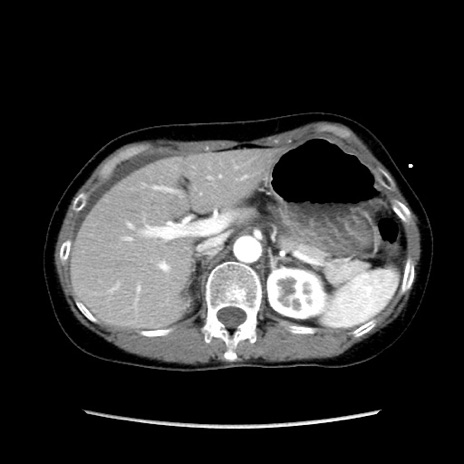

症例32(横断像)

【症例】40歳代 女性

【主訴】上腹部痛、嘔気・嘔吐

【現病歴】約9時間前頃から急に上腹部痛、嘔気、嘔吐が出現。改善しないため救急要請。

【既往歴】子宮頚癌(広汎子宮全摘術、放射線療法)、腸閉塞

【身体所見】腹部:平坦、軟、腸雑音亢進、上腹部を中心に腹部全体に圧痛あり。

【データ】WBC 8400、CRP 0.03